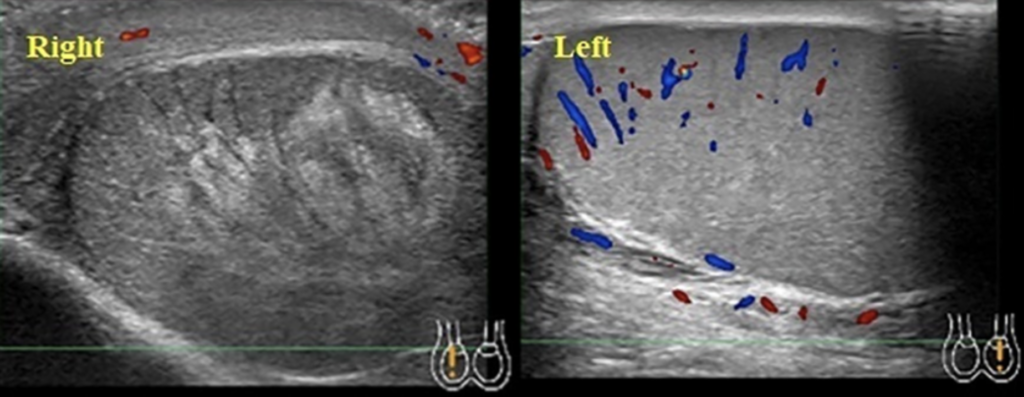

Epididymo-orchitis. Normal right testis (A), with left testis (B) showing epididymis (thick arrow), increased blood flow, and reactive hydrocele (thin arrow). Source: Mandava et al., 2020.

- Findings: In epididymitis, there is typically enlargement of the epididymal head on ultrasound. If there is accompanying orchitis, Doppler will show asymmetrically increased color flow in the affected testis.

- Sensitivity: 78.8%; Specificity: 98.1% (Zitek et al., 2020)

- Management: Typically a combination of antibiotics, analgesics, and supportive management.